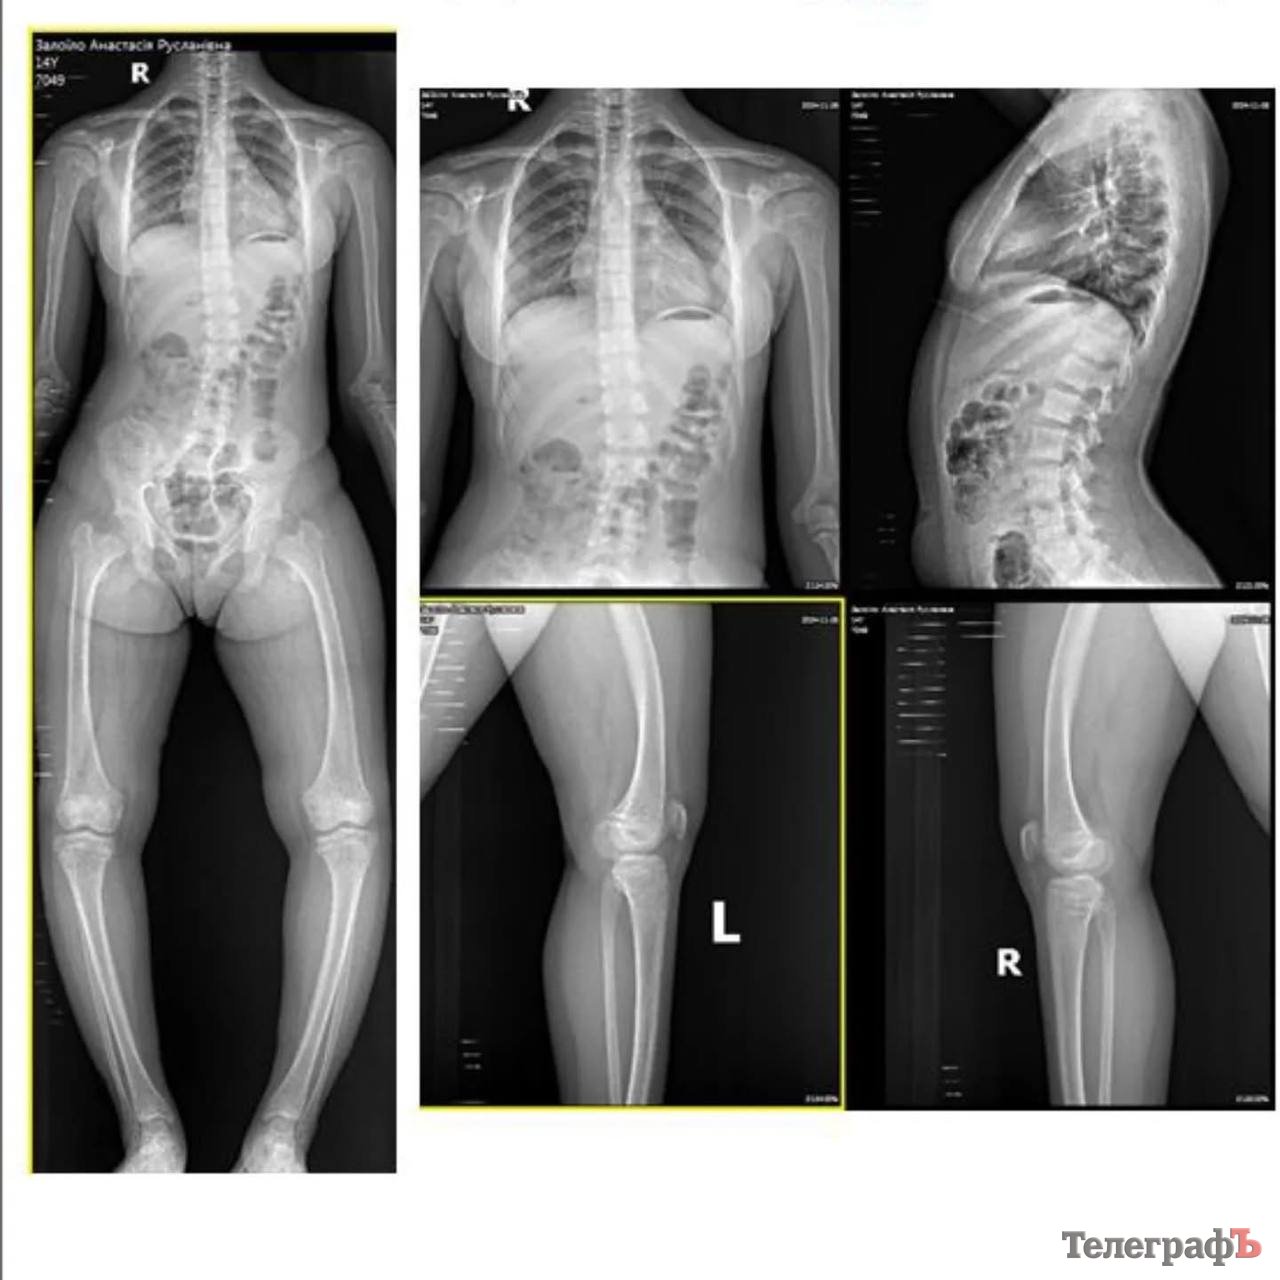

Анастасія Залоїло з Кременчука страждає на рідкісну спадкову хворобу. Їй потрібна операція на ноги. Родина просить допомоги небайдужих

Юна кременчужанка, 15-річна Анастасія Залоїло, потребує нашої допомоги. Дівчина страждає на спадкову хворобу: метафізарна дисплазія, фосфат діабет. Простими словами в Анастасії криві ніжки.

Щоб вирівняти ноги й впевнено ходити, їй потрібно зробити операцію. Мама дівчини, Ірина Залоїло, звертається з проханням до всіх небайдужих: